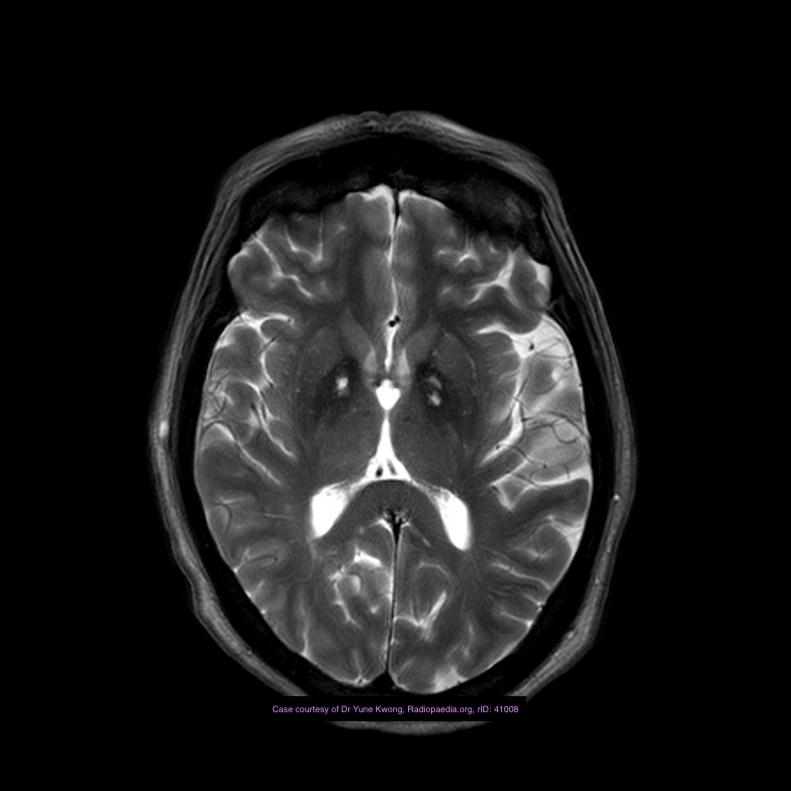

MRI

They appear as subtle lesions with no mass effect.

T1: typically iso to low signal compared with brain parenchyma

T2: normal or slightly increased signal intensity

FLAIR: normal or slightly increased signal intensity

T2*: low signal intensity

thought to be due to deoxyhaemoglobin from sluggish flow, not haemorrhage 2